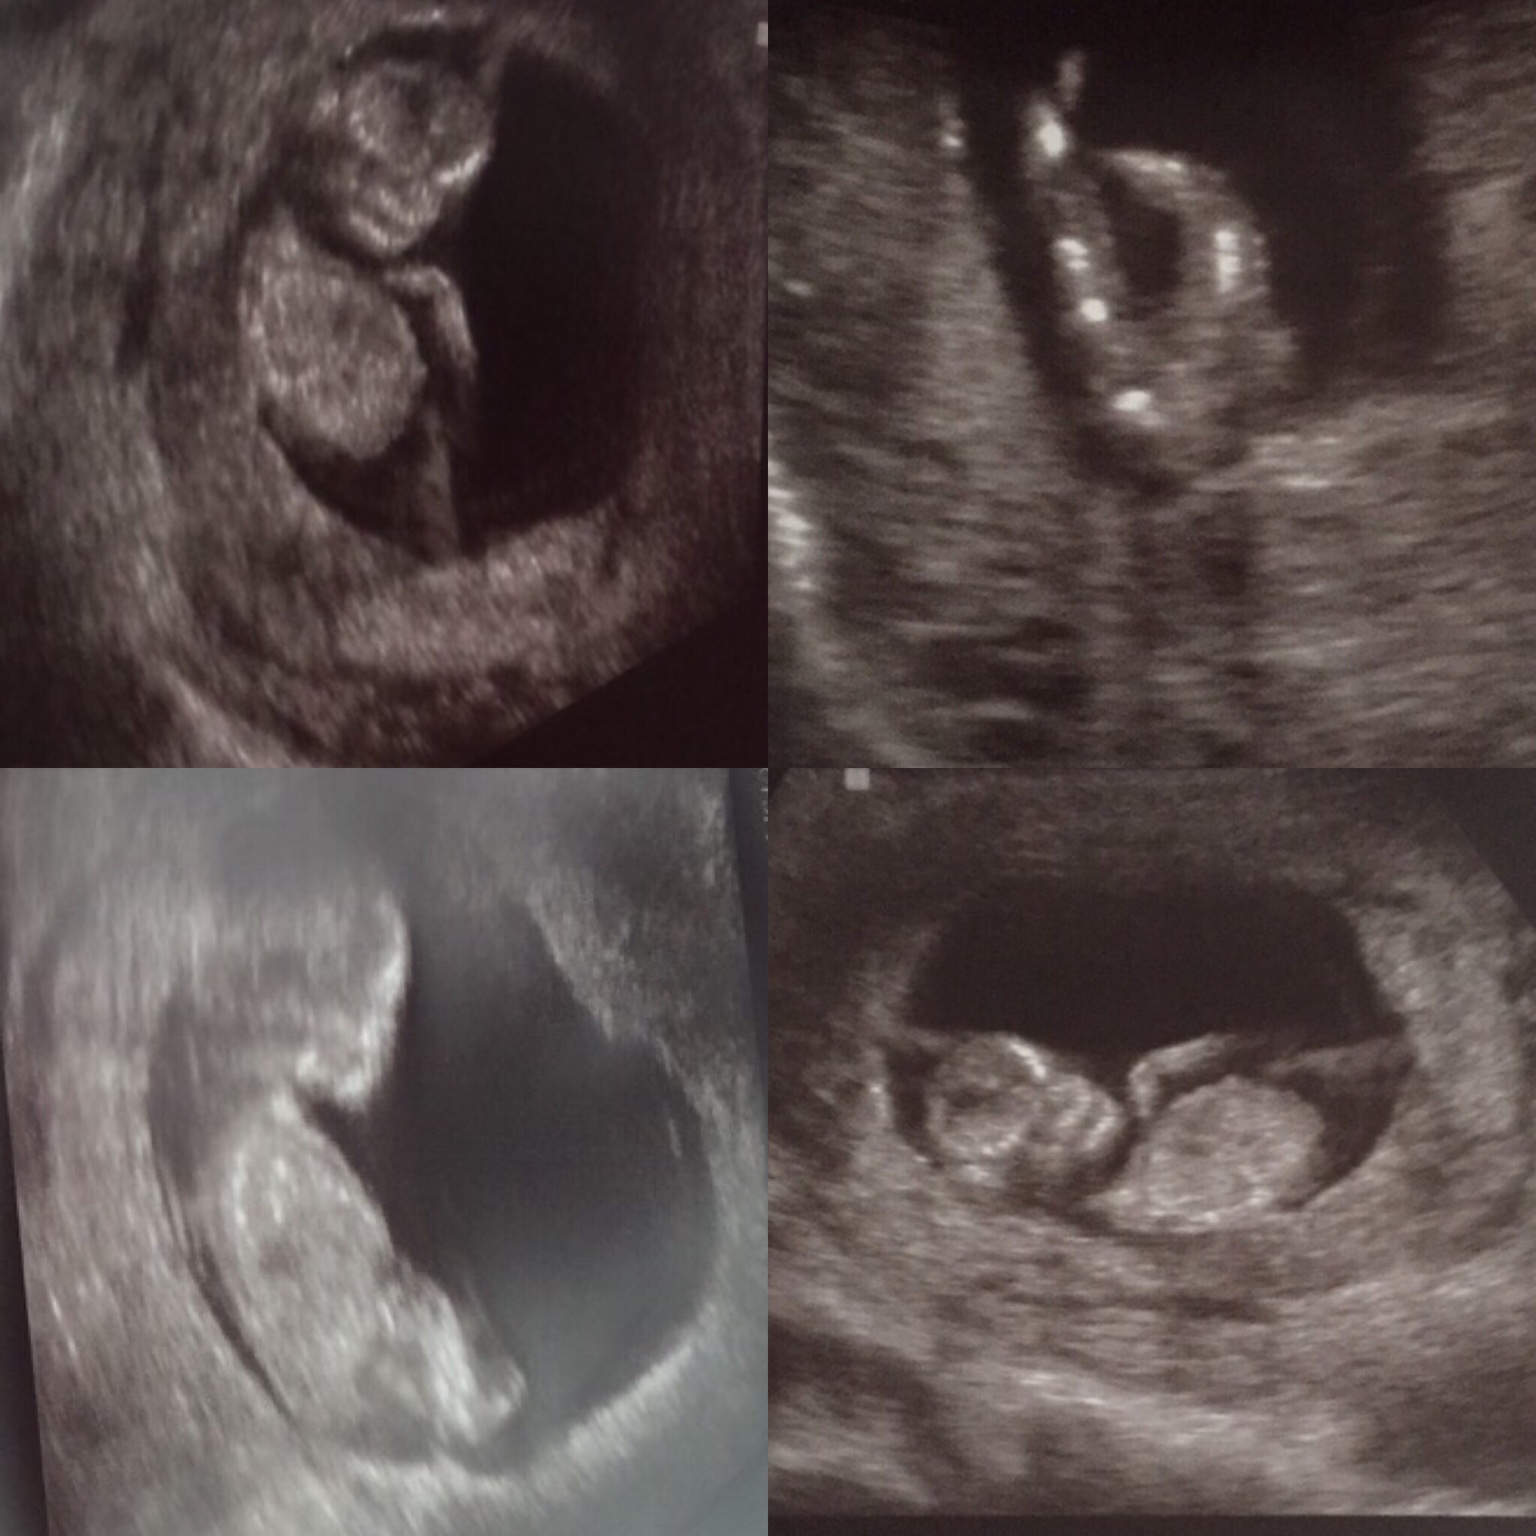

what is gestation on these pics??